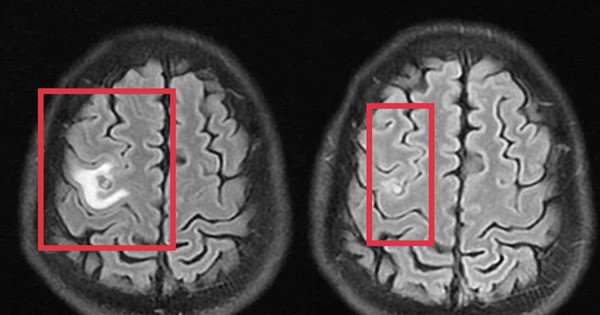

Bệnh nhân nam 39 tuổi nhập viện vì co giật, đau đầu, tổn thương não nghi ngờ u não, không ngờ bác sĩ phát hiện bí mật bên trong.